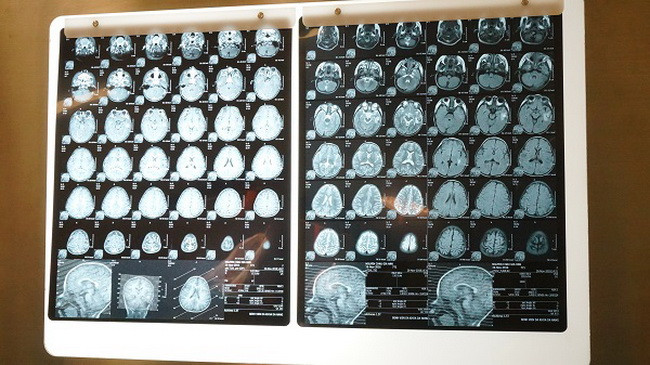

| Phim chụp vùng đầu của bệnh nhi G.V. |

Theo chia sẻ của chị L. - mẹ bé G.V, trước khi phát hiện khối u mạch máu não, bé sinh hoạt phát triển bình thường như bao trẻ khác. Khi đang chạy nhảy nô đùa, bé đột nhiên nôn mửa, người tê liệt, co giật. Gia đình đưa vào bệnh viện tại Đà Nẵng cấp cứu. Kết quả chụp CT cho thấy, bé bị khối u ở mạch máu não. Sau đó, gia đình quyết định đưa bé vào BV Quốc tế City (TPHCM) để phẫu thuật.